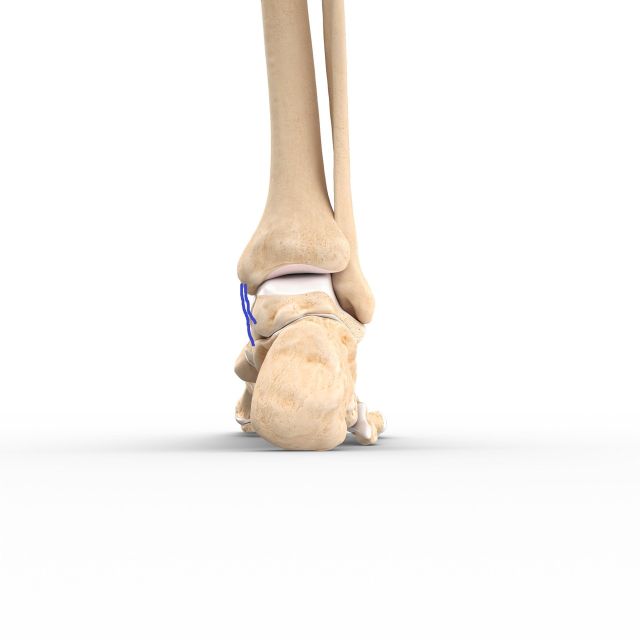

Bei frischen Verletzungen können meistens Bandanteile mit Fäden augmentiert und am Knochen wieder fixiert werden. Mitunter erfolgt die Fixierung des Bandes mittels im Knochen eingebrachter Ankersysteme, über die das Band angenäht werden kann. Um ein Ausreißen der Anker bzw Fäden verhindern zu können, werden üblicherweise „Stellschrauben", die das Wadenbein am Schienbein etwas oberhalb des Sprunggelenks fixieren, gesetzt.

Diese Schrauben müssen vor Beginn der Gehbelastung in aller Regel entfernt wieder werden. Alternativ kann ein sogenanntes Tight Rope, ein Kunstband, das über einen Bohrkanal das Schien- am Wadenbein fixiert, verwendet werden.